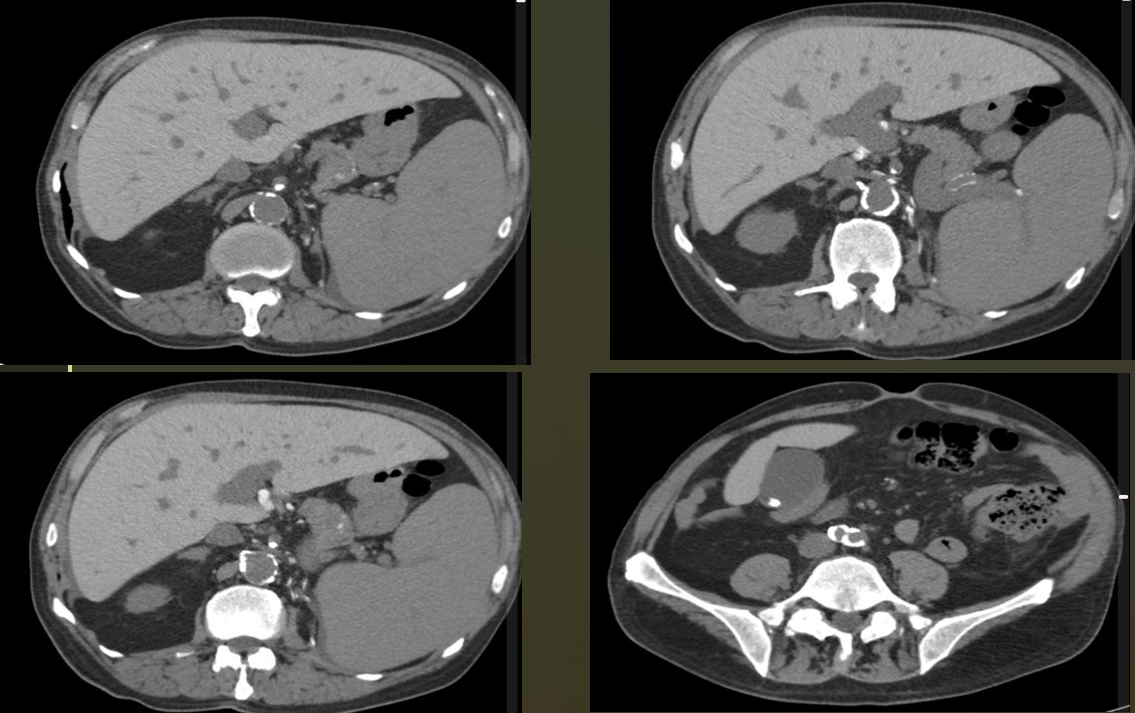

Homem, 74 anos, fibrilação atrial.

Dor abdominal aguda.

Infarto tromboembólico da artéria renal direita.

Região hipodensa com defeito de realce em forma de cunha.

Sinal do realce cortical ocorre geralmente após 24 horas do infarto e consiste no realce da margem periférica do rim na fase nefrográfica, no contexto isquemico. Ocorre em cerca de 50% dos casos.